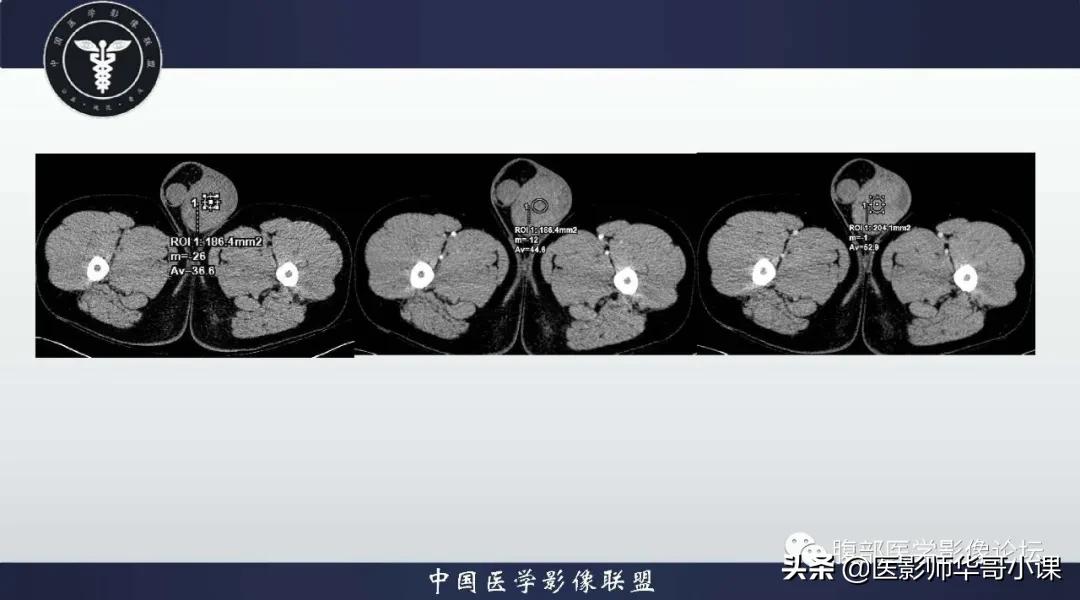

影像学表现与病理相符合,MRI显示肿块呈多发结节状,T1WI 呈等信号,与正常*丸睾**T1WI 信号相等,T2WI 信号低于正常*丸睾**组织, 瘤内纤维血管分隔数量不等,粗细不均,增强扫描纤维血管分隔强化高于肿瘤组织 。由于肿块浸润受到白膜限制,其轮廓一般清楚。大部分文献报道精原细胞瘤较少出现坏死、出血。